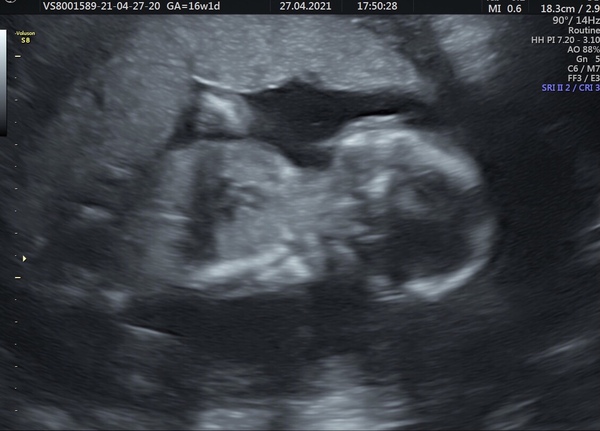

I completely forgot to post on here last night because I was so overwhelmed and relieved 🙈 all went well at our scan thankfully. She checked and confirmed legs, arms, feet and hands looked fine. The lungs and bladder were working as they should be, the head measured fine and there was enough fluid around baby. She was very reassuring and also played the heartbeat for me and we got one of the little bears with it 😊 scan photos aren’t the clearest as baby was wriggling a lot, doing a handstand, and turning their back 🙈 and we found out that it’s a girl! 😁